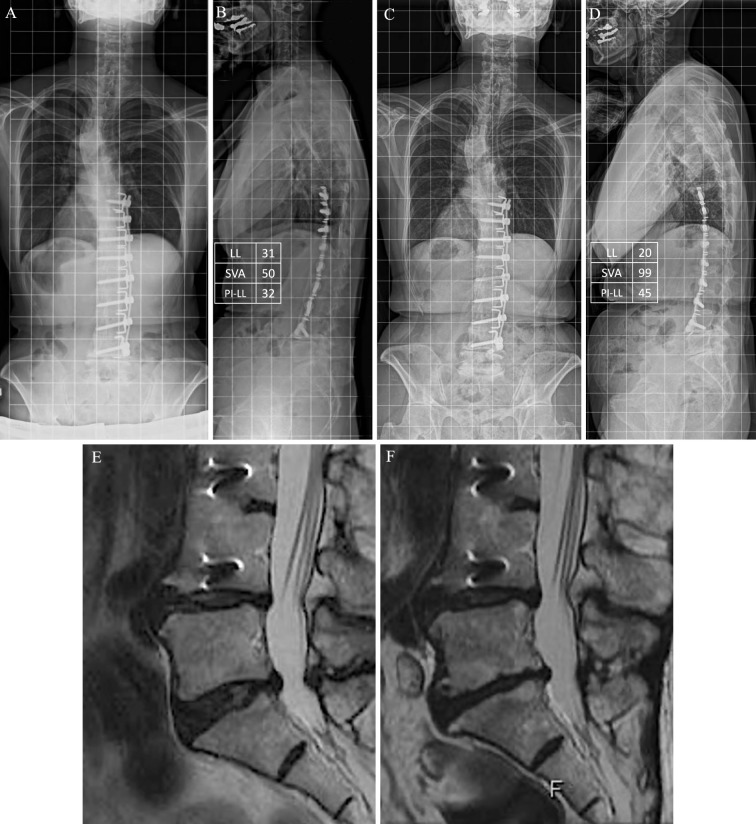

简介:本研究旨在确定中老年青少年特发性脊柱侧凸(AIS)患者术后椎间盘退变(DD)的相关因素。方法:在1968年至1988年期间接受脊柱融合手术的252名AIS患者被纳入这项基于调查的研究。患者的平均随访期为40.9年,通过腰椎磁共振成像(MRI)、放射学评估和患者报告的结果测量(PROMs)对患者进行评估。采用Pfirrmann分级系统对DD进行评价。我们分析了手术水平、矢状面对准和前列腺癌等各种因素与DD的关系。结果:在21名接受了先前(2014年至2016年)和最新(2022年)调查的参与者中,DD的患病率从上一次调查的66.7%上升到最新调查的76.9%。Pfirrmann disc总分从3.2显著提高到3.5。矢状面排列参数,如矢状垂直轴(SVA)、骨盆发生率减去腰椎前凸(PI-LL)和骨盆倾斜(PT),随着时间的推移而恶化。脊柱侧凸研究学会-22疼痛问卷、Roland-Morris失能问卷、Oswestry失能指数得分均较前一次明显下降。L4或更低和L3或更高的下固定椎体(LIV)患者的比较显示,L4或更低组的椎间盘评分明显更高,DD患病率为100%。与DD相关的因素包括L4或更低的LIV,较小的LL,较大的胸腰椎后凸,SVA, PI-LL和pt增加。结论:本研究表明,维持L3或更高的LIV,实现良好的矢状位对齐,维持LL可能有助于预防AIS患者的长期DD。

Results: Among the 21 participants who underwent both previous (conducted from 2014 to 2016) and latest surveys (conducted in 2022), the prevalence of DD increased from 66.7% in the previous survey to 76.9% in the latest survey. The overall Pfirrmann disc score significantly increased from 3.2 to 3.5. Sagittal alignment parameters, such as sagittal vertical axis (SVA), pelvic incidence minus lumbar lordosis (PI-LL), and pelvic tilt (PT), worsened over time. Scores in the Scoliosis Research Society-22 Questionnaire pain, Roland-Morris Disability Questionnaire, and Oswestry Disability Index were significantly worse in the latest survey than in the previous one. Comparison between patients with the lower instrumented vertebra (LIV) at L4 or lower and L3 or higher revealed significantly higher disc scores and 100% prevalence of DD in the L4 or lower group. Factors associated with DD included LIV at L4 or lower, smaller LL, larger thoracolumbar kyphosis, and increased SVA, PI-LL, and PT.